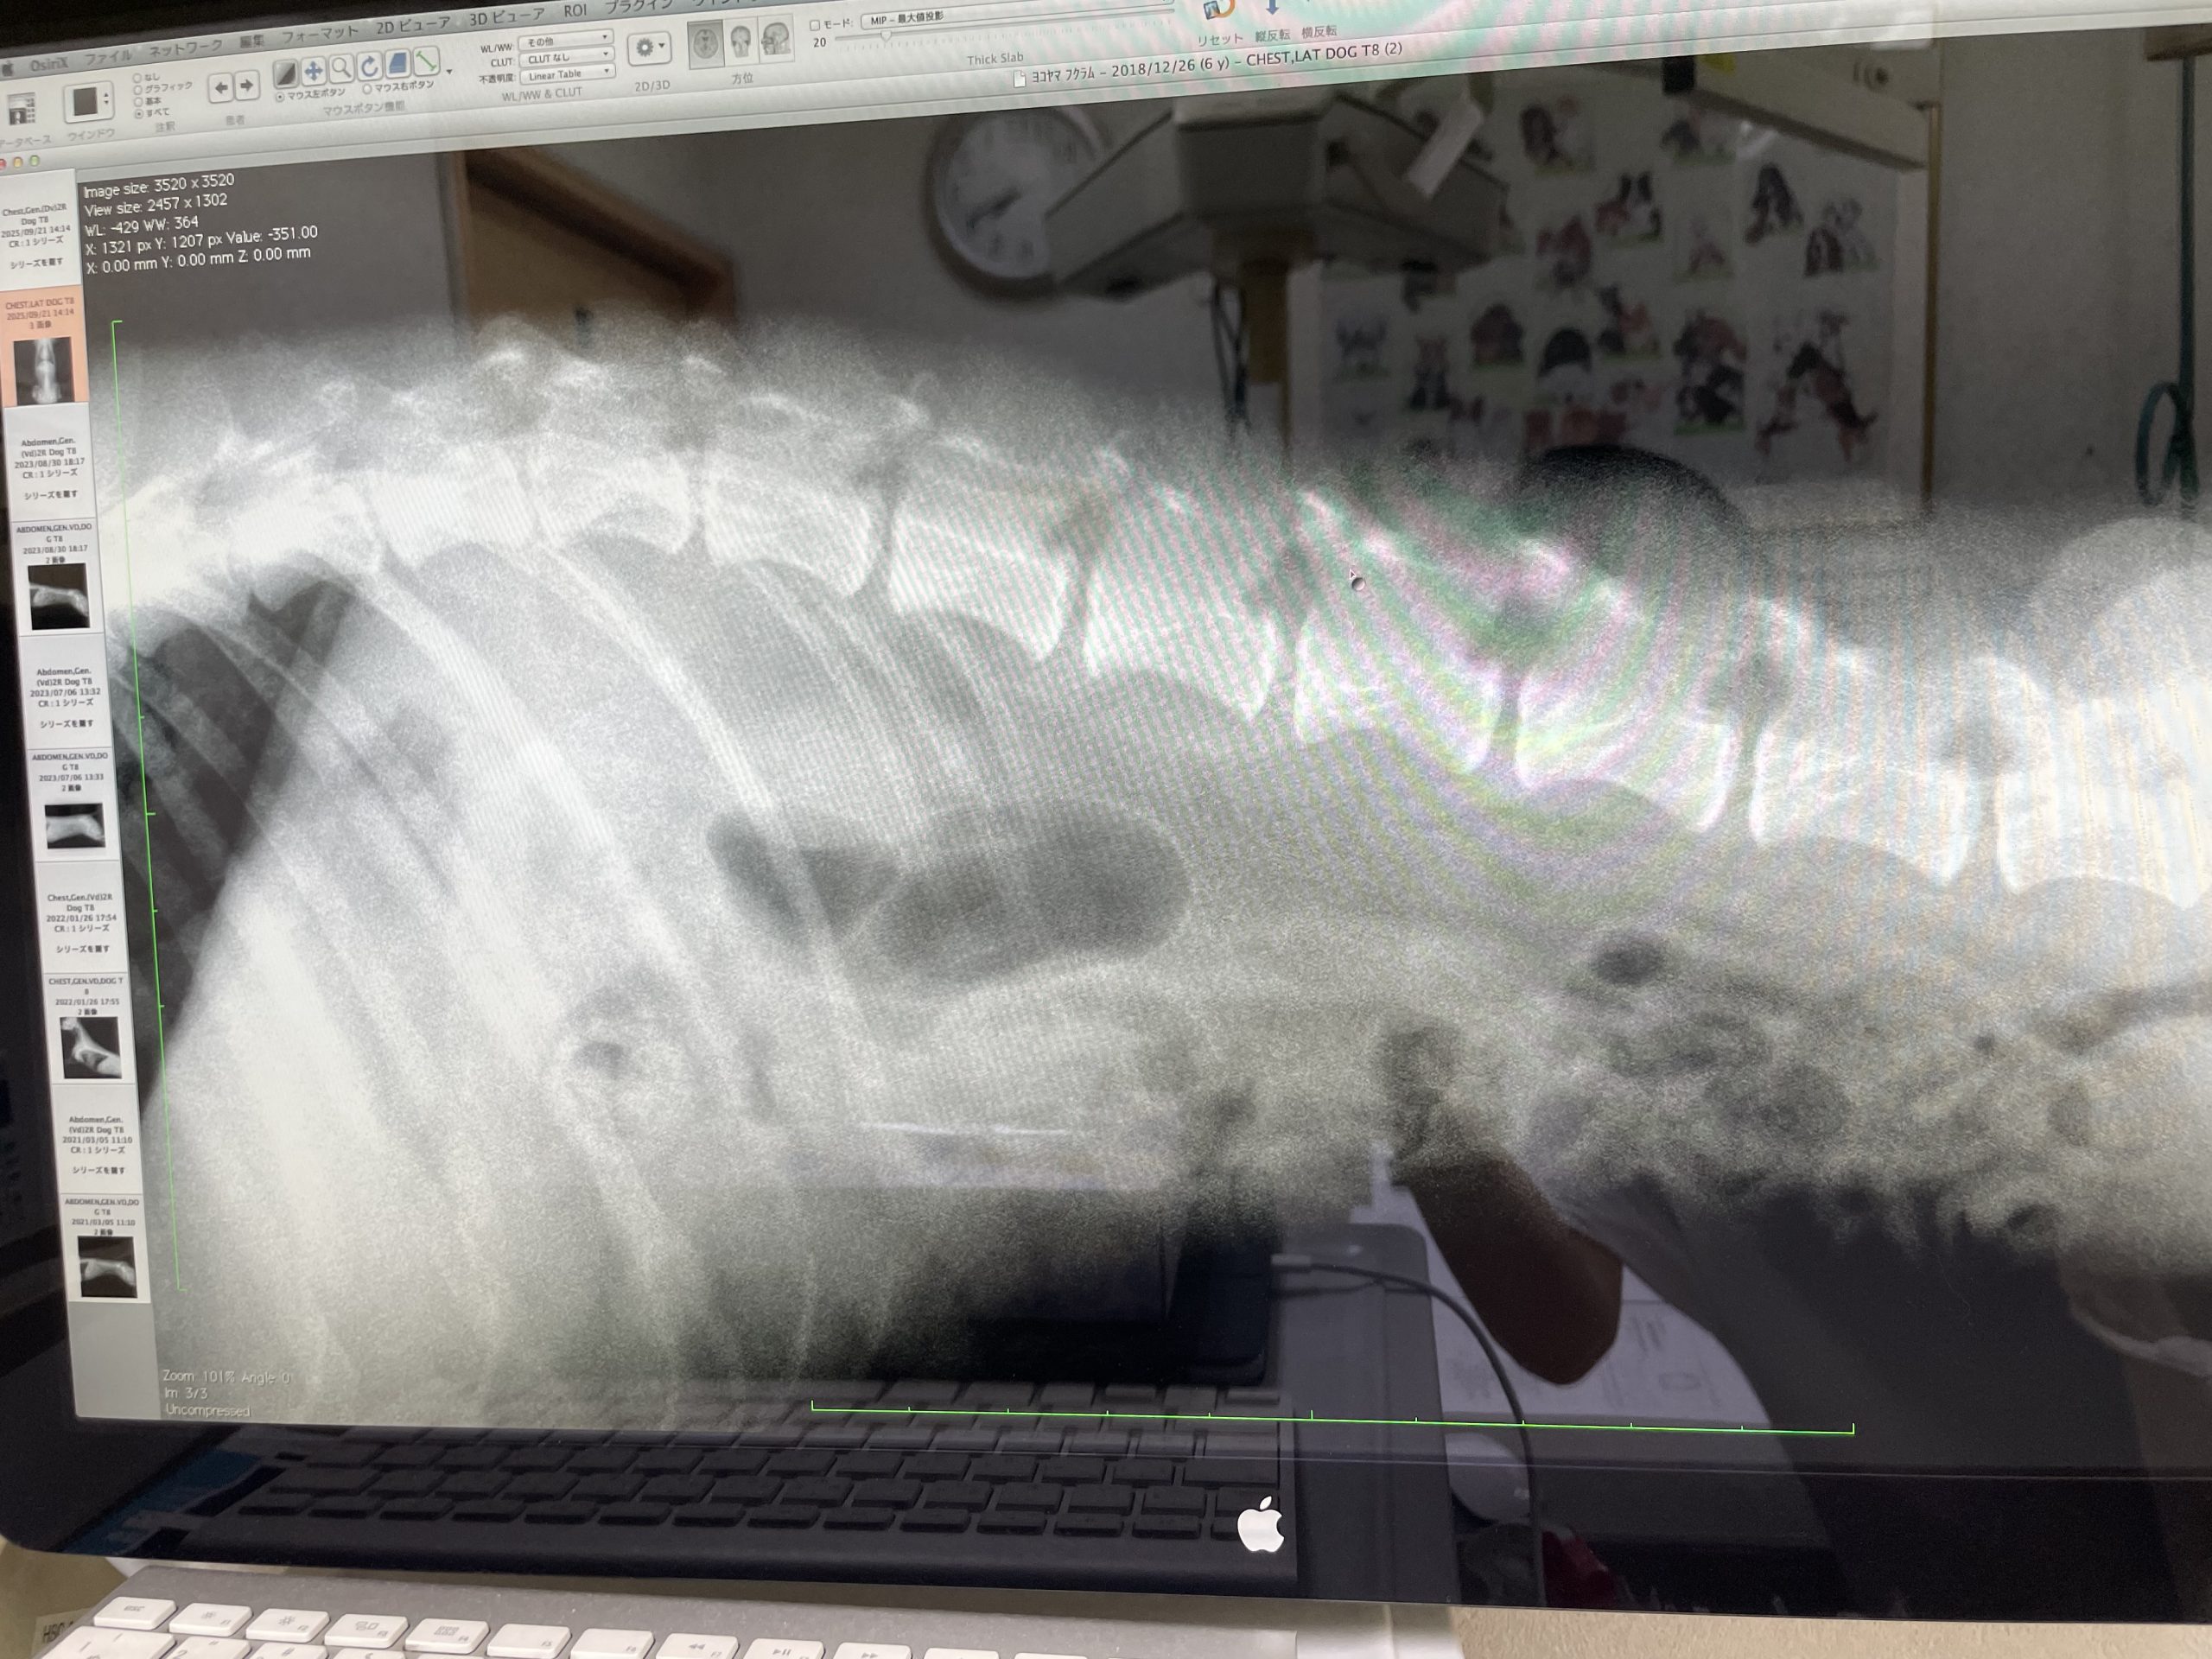

横から見た背骨、拡大してるので

写真に見えない所でまだ骨が続いてるけど

この画面に写ってる部分では

左から数えて6個が手術で骨を

削ってる所だそうです。

(右の方がお尻)

お尻側の骨と骨の隙間は適度に開いてるから

この辺は大丈夫そうだよねって感じらしい。

絶対とは言えないですが(^◇^;)

手術したとこ、

骨と骨の隙間が全然ないの分かりますか?

緩衝材?みたいのが殆どないんだそう。